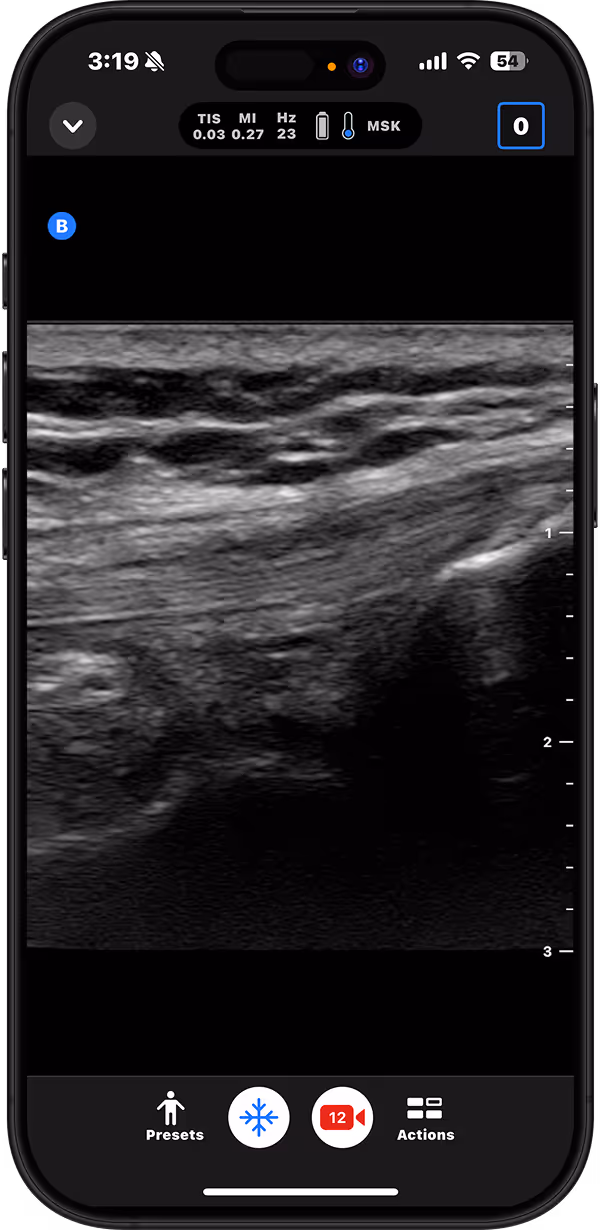

Identify joint effusions, guide aspirations, and differentiate cellulitis from abscess.

Patellar Tendon